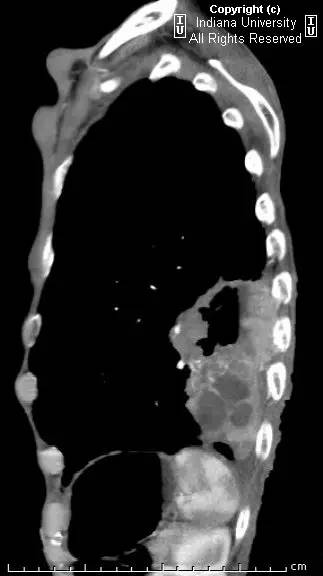

胸片示肺内高度膨胀性病变,膈肌扁平。左后胸部可见较大卵圆形不透亮区并液平面。CT示左肺下叶近后胸壁较大厚壁肿块并部分空洞形成,实性部分不均质强化。右肺下叶可见分叶状结节。左前下少量气胸。

【诊断】鳞状细胞肺癌并后部阻塞性肺炎